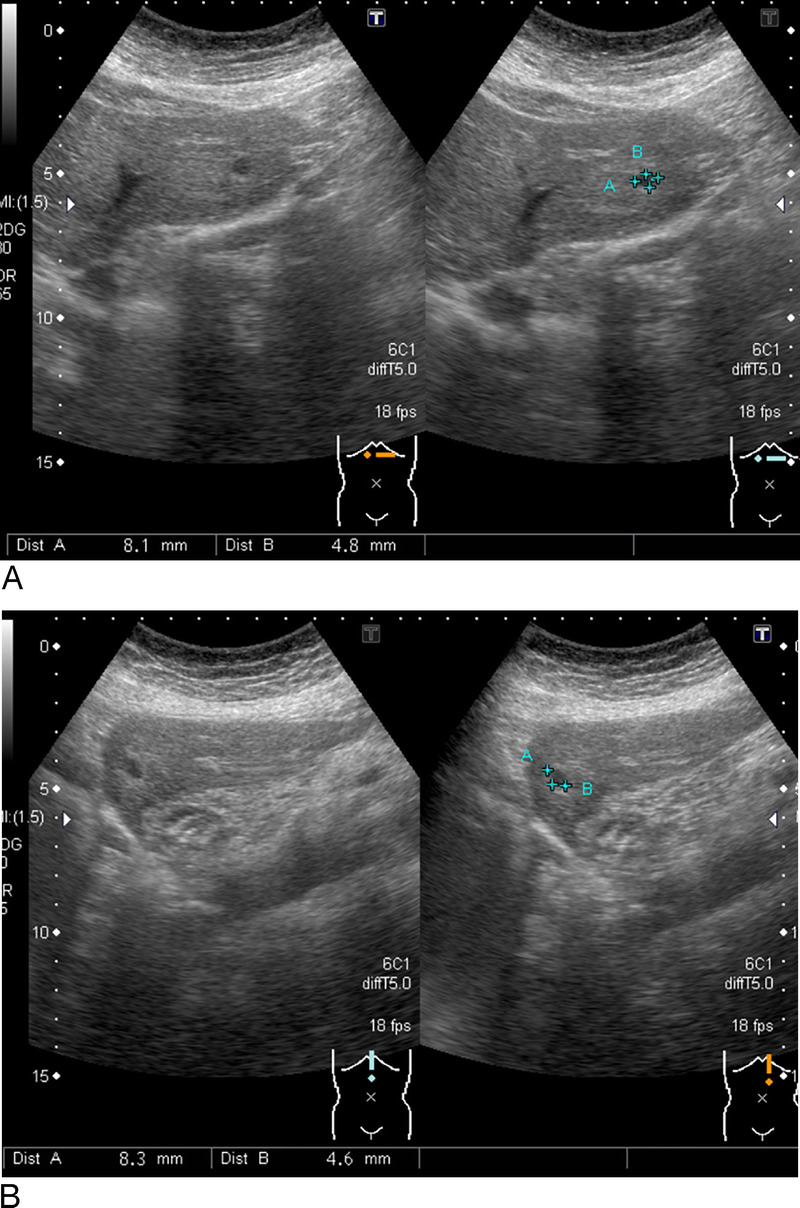

A suspected case of hepatic reactive lymphoid hyperplasia in which EUS-fine needle aspiration contributed to the diagnosis.

疑似肝反应性淋巴样增生病例,eus细针穿刺诊断。